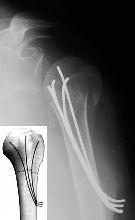

FRACTURAS 1/3 PROX DE HUMEROFRACTURAS 1/3 PROX DE HUMERO ENCLAVADO ENDOMEDULAR RETROGRADO. ENCLAVADO ENDOMEDULAR RETROGRADO. ENCLAVADO ENDOMEDULAR FLEXIBLE. Tipo Ender. ENCLAVADO ENDOMEDULAR FLEXIBLE. Tipo Ender.